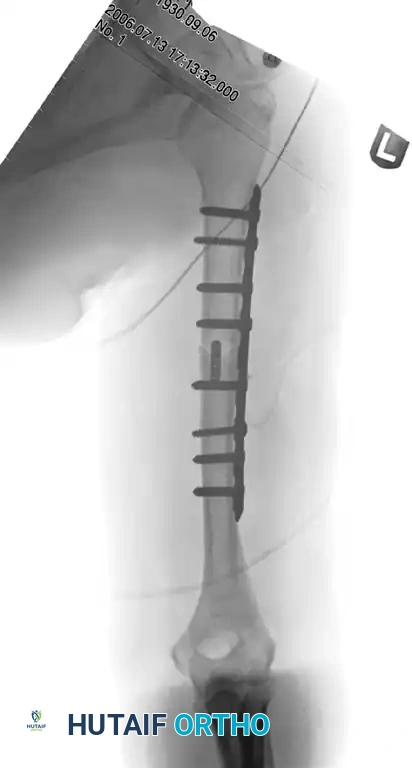

Figure 57-39 A: Fracture of the distal third of the humeral shaft.

Figure 57-39 B: Postoperative radiograph after plate fixation through a posterior triceps-splitting approach.